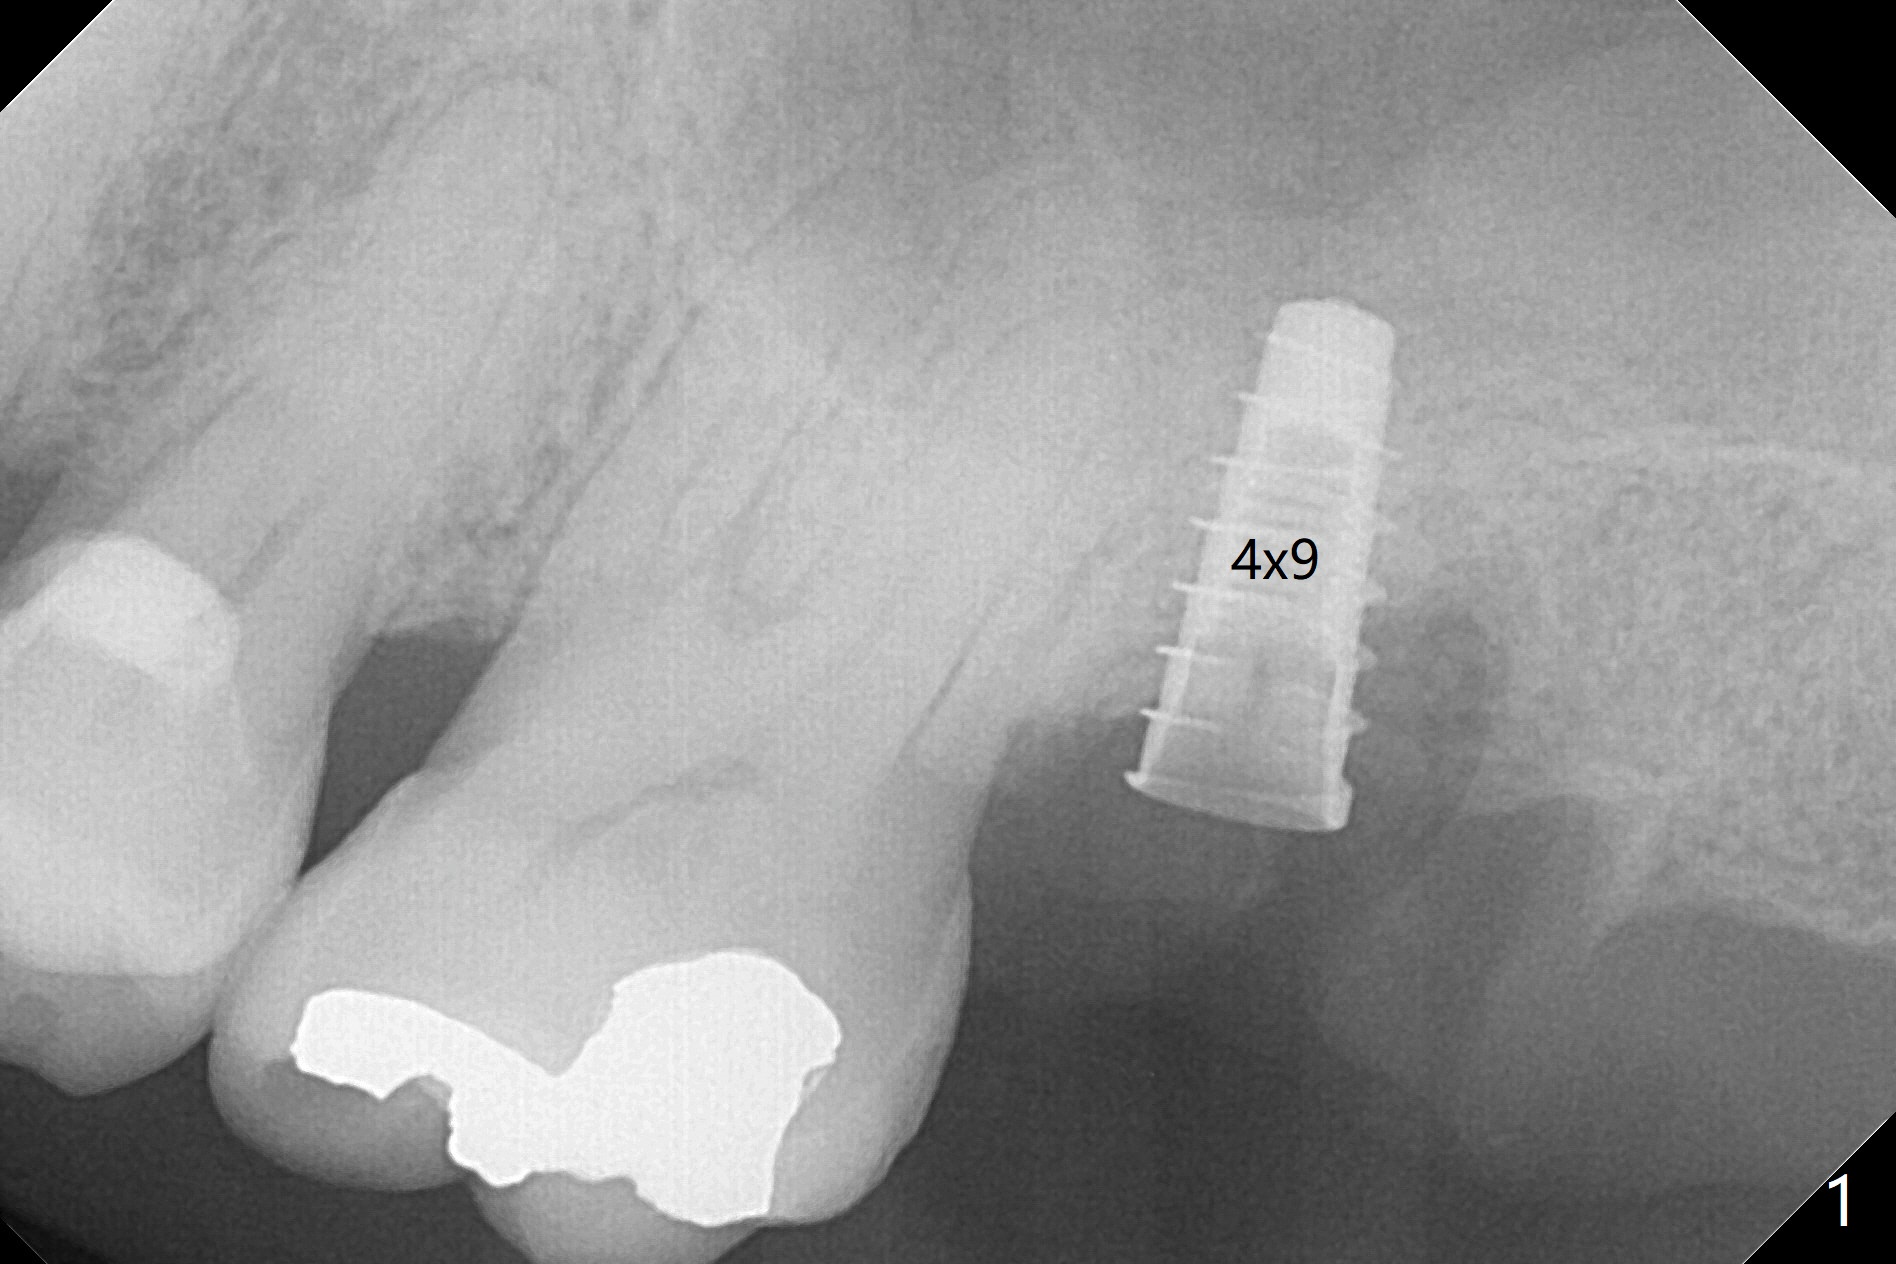

Designed osteotomy depth is 7.3 mm IS drill with 4 rings at #15. In fact osteotomy is created using 2.2 mm drill with 2 rings (sinus membrane barely visible from the osteotomy) and 3-4 mm ones with 3 rings. With an amalgam carrier of bone graft, sinus lift is initiated with 4x9 mm dummy implant (Fig.1). After loaded with totally 5 amalgam carriers of bone graft repeatedly with the 4x9 mm dummy implant, a 5x9 mm implant is placed with ~ 25 Ncm. After insertion of a 6x4(2) mm abutment, sticky bone cut into pieces (Fig.2) is inserted to peri implant space (Fig.3 *), followed by PRF and an immediate provisional. The latter dislodges 7 days postop; the socket starts to heal (Fig.4); the bone graft seems to be fixed in place. The provisional is reseated (no cement, Fig.5) without fear of its dislodgement again. The patient returns for cleaning 1 year 7 months postop (Fig.6,7). The socket heals, while the abutment is incompletely seated (Fig.7 <). Percussion at #18 disappears post RCT, whereas periapical radiolucency appears post RCT (compare Fig.8,9). When the 6x4(2) mm incompletely seated abutment is removed, the implant well is dirty. The smaller abutment with longer cuff is seated fully (Fig.10).